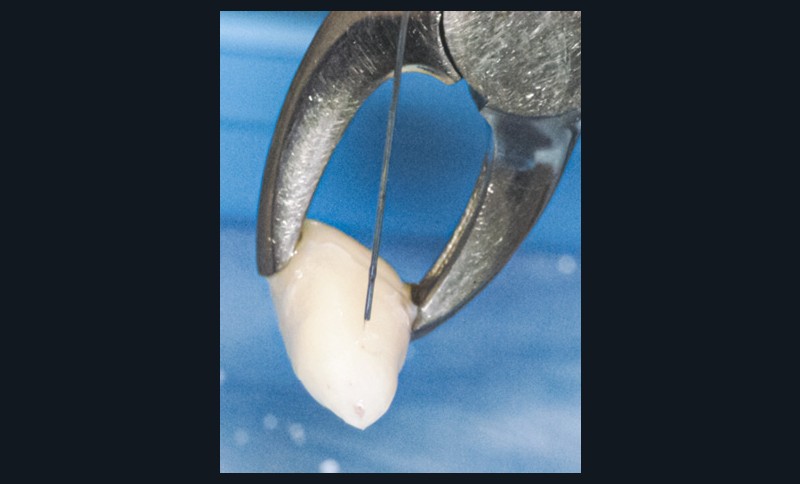

Enfant de 9 ans dont une incisive centrale maxillaire a été expulsée en jouant au football. Appel immédiat de la mère à qui l’on conseille de conserver la dent expulsée dans du sérum physiologique (fig. 1). Le temps extra-alvéolaire à sec a été inférieur à 5 minutes. Le patient arrive 40 minutes après le traumatisme dans l’Unité d’Odontologie pédiatrique. Après interrogatoire, examen clinique et radiographique, un rinçage de l’alvéole est effectué et la dent est réimplantée le plus rapidement possible (fig. 2). Une contention semi-rigide est ensuite placée (fig. 2). La dent étant mature, la prise en charge endodontique (séance de Ca(OH)2 puis obturation à la gutta percha) débute deux semaines plus tard (fig. 3 et 4) afin de limiter les risques d’infection, de résorption. Le suivi sur quatre années montre une dent fonctionnelle, sans ankylose ni résorption radiculaire ou osseuse.